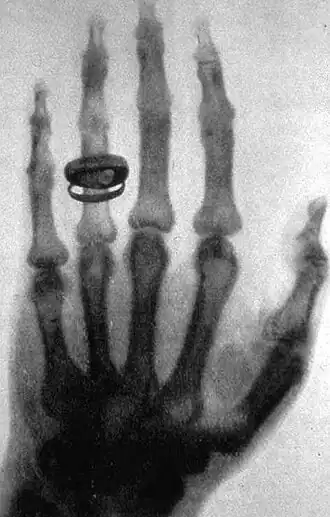

История рентгенологии начинается в 1895 году, когда Вильгельм Конрад Рентген впервые зарегистрировал затемнение фотопластинки под действием рентгеновского излучения. Им же было обнаружено, что при прохождении рентгеновских лучей через ткани кисти на фотопластинке формируется изображение костного скелета (см. Рука с кольцами). Это открытие стало первым в мире методом медицинской визуализации, до этого нельзя было прижизненно, не инвазивно получить изображение органов и тканей. Рентгенография очень быстро распространилась по всему миру. В 1896 году в России был сделан первый рентгеновский снимок[1].